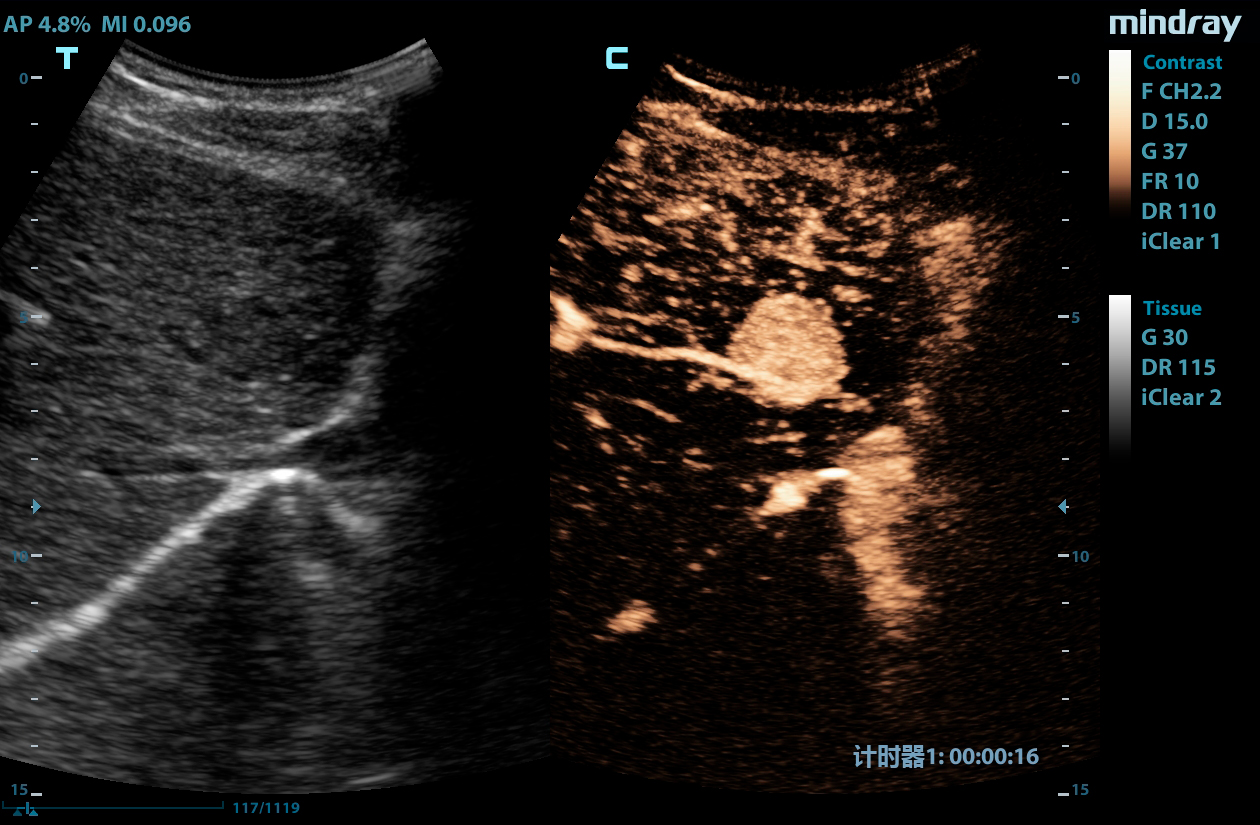

LVO with Stress Echocardiography

The combination of LVO during stress examinations enhances differentiation between tissue and the blood pool, providing better visualization of the endocardium. This package includes customizable user protocols, flexible wall motion scoring, and a comprehensive reporting suite.